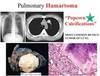

Benign leasions of lungs

Granuloma (TB, fungus, sacro)

Bronchial harmatoma